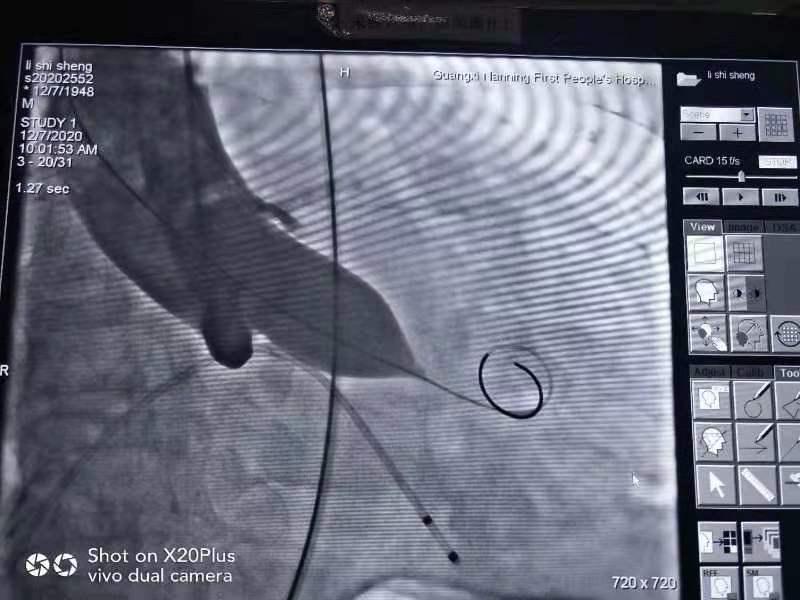

TAVR术中

扩张主动脉瓣

胸心血管外科团队经过药物控制肺部感染和手术前的精心准备和风险评估,12月7日上午,经过95分钟的奋战,经股动脉微创的方式扩张开狭窄的主动脉瓣,将一枚23号人工主动脉瓣膜植入、代替原病变的主动脉瓣开始正常工作。植入位置恰好、各项指标正常,将近70mmHg的跨主动脉瓣压差瞬间恢复至17mmHg,心脏功能恢复正常。